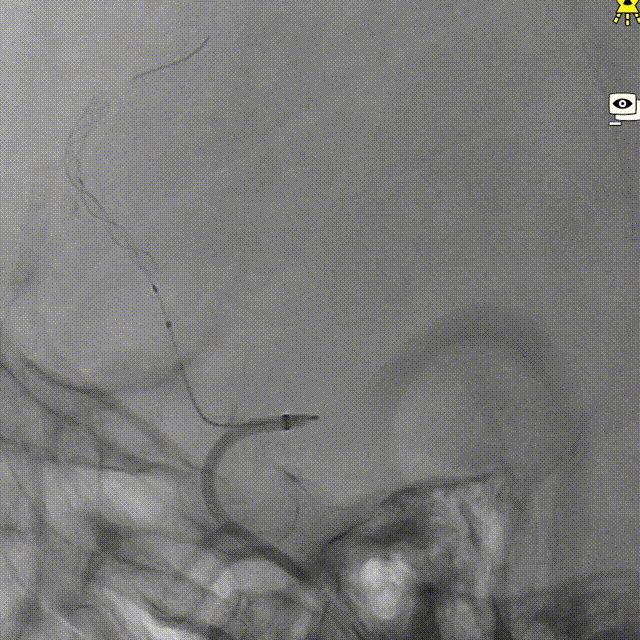

回撤推送导丝及微导管。

术后造影。

术后正侧位造影。

术后VASO CT。

强易达(Choydar)血流导向密网支架材质是镍钛合金,输送易到位;头端导丝、50%释放点、100%释放点清晰,便于观察支架位置。

50%Mark点可帮助分析后半段打开后的尾端位置,近端血管较粗考虑支架短缩,也可调整支架的50%Mark点置于偏近端一些。

支架由2对4根铂钨合金显影丝以对向排列的方式,混合编入支架主体,呈3D立体显影效果,便于观察支架贴壁情况。